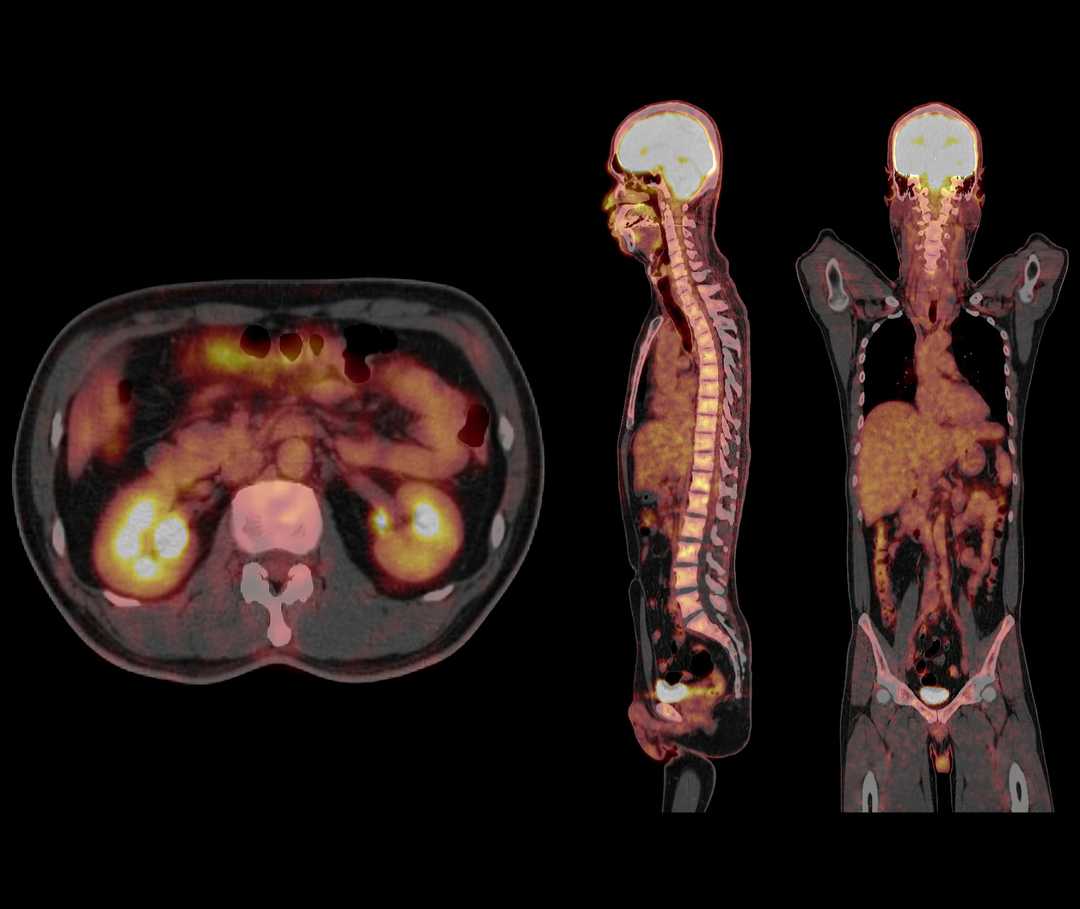

Bei der nuklearmedizinischen Diagnostik wird den Patientinnen und Patienten eine radioaktive Substanz verabreicht. Diese Substanz gelangt in die betroffene Zielstruktur (z. B. Organ oder Tumorzellen) und lagert sich dort an, bzw. zeigt eine erhöhte Stoffwechselaktivität. Durch den Einsatz bildgebender Verfahren lässt sich dann erkennen, wo es bösartige Veränderungen und Metastasen im Körper gibt. Während bildgebende Verfahren, wie bspw. das Röntgen oder die Computertomographie, die Anatomie des Körpers darstellen, lassen sich mit nuklearmedizinischen Untersuchungen die biochemischen Prozesse der betroffenen Zielstruktur darstellen.

CT Scan eines Patienten